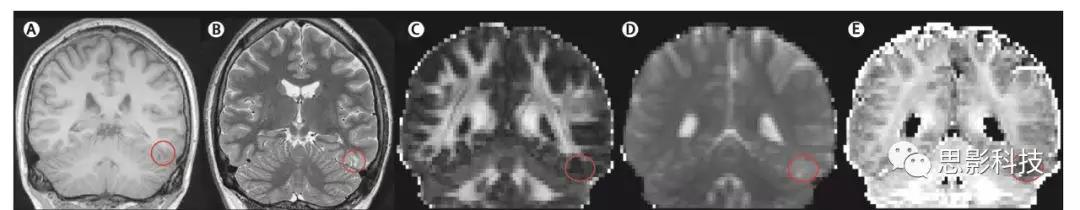

局灶性皮質(zhì)發(fā)育不良伴皮質(zhì)增厚和模糊的灰質(zhì)-白質(zhì)交界, T1加權(quán)成像(A)上(圓圈),在T2FLAIR(B)上呈高信號(hào)。右海馬硬化伴體積損失在T1加權(quán)成像(C)(圓圈),在T2加權(quán)(D)上高信號(hào)強(qiáng)度,和T2加權(quán)成像(E)上內(nèi)部結(jié)構(gòu)的損失。T2*加權(quán)圖像(F)上,左側(cè)顳下回海綿狀瘤(圓圈狀)可以被視為信號(hào)丟失區(qū)。(G)將基于體素的圖像后處理方法應(yīng)用于一名38歲婦女的T1等體素序列MRI數(shù)據(jù),能清楚顯示交界圖像(模糊的灰質(zhì)-白質(zhì)交界)和延伸圖像(灰質(zhì)異常延伸至白質(zhì))上的局灶性皮質(zhì)發(fā)育不良。相應(yīng)的切片顯示在原始T1加權(quán)圖像上。(A—F)在3T掃描儀上獲得(A,C)三維快速損毀梯度回波T1加權(quán)序列(體素0.9375×0.9375×1.1mm),(B)軸向和(D)斜冠狀T2FLAIR序列(體素:0.9375×0.9375×5mm),(E)使用螺旋槳技術(shù)的斜冠狀位T2加權(quán)序列(層面分辨率為0.43×0.43mm,層厚為2mm)和(F)冠狀快速梯度回波T2加權(quán)序列(層面分辨率為0.9375×0.9375mm,層厚為5mm)。對(duì)于所有圖像,圖像的左側(cè)=大腦的右側(cè)。

皮質(zhì)異常,特別是局灶性皮質(zhì)發(fā)育不良,是許多兒科疾病的基礎(chǔ),約占成人MRI陰性頑固性癲癇病患者的四分之一。異常影像學(xué)表現(xiàn)包括局灶性皮質(zhì)增厚,灰白質(zhì)交界處模糊, T2加權(quán)或FLAIR圖像上高信號(hào)。然而,MRI結(jié)構(gòu)通常正常,尤其是I型局灶性皮質(zhì)發(fā)育不良。當(dāng)位于腦溝深處時(shí),80%以上的局灶性皮質(zhì)發(fā)育不良病灶不能被視覺(jué)檢測(cè)到。成像采集技術(shù)的進(jìn)步使我們能夠檢測(cè)到先前未確認(rèn)的結(jié)構(gòu)異常,如局灶性皮質(zhì)發(fā)育不良。例如,雙反轉(zhuǎn)恢復(fù)能抑制腦脊液和白質(zhì)的信號(hào),從而改善大腦皮層的對(duì)比度。動(dòng)脈自旋標(biāo)記可顯示組織灌注,血流減少可能與局灶性皮質(zhì)發(fā)育不良有關(guān)。擴(kuò)散成像方法的發(fā)展,如軸突定向彌散和密度成像或擴(kuò)散峰度成像,提供了組織微結(jié)構(gòu)的更多細(xì)節(jié),提高了檢測(cè)局灶性皮質(zhì)發(fā)育不良的敏感性(圖3)。

一名27歲男性,左側(cè)顳下回局灶性皮質(zhì)發(fā)育異常。在3D-T1WI(A)和T2WI(B)圖以及分?jǐn)?shù)各向異性圖(C)和平均擴(kuò)散率圖(D)的標(biāo)準(zhǔn)擴(kuò)散圖像上,該區(qū)域(帶圓圈)的顯示不清楚。局灶性皮質(zhì)發(fā)育不良在神經(jīng)突定向彌散和密度成像上很容易看到細(xì)胞內(nèi)體積分?jǐn)?shù)的降低,這是一種先進(jìn)的MRI序列(E)

基于體素的形態(tài)學(xué)分析(VBM)最初應(yīng)用于T1加權(quán)圖像,用于組間灰白質(zhì)的定量分析,隨后用于個(gè)體與對(duì)照組的比較。初步研究結(jié)果表明,27例局灶性皮質(zhì)發(fā)育不良患者中有21例被正確識(shí)別?;隗w素的分析已經(jīng)被應(yīng)用于T2弛豫圖和FLAIR圖像,以提高對(duì)局灶性皮質(zhì)發(fā)育不良和MRI陰性者異常的檢測(cè)靈敏度。通過(guò)基于VBM的形態(tài)測(cè)量分析程序產(chǎn)生一個(gè)交界圖以突出灰白色物質(zhì)邊界的模糊和一個(gè)延伸圖以描繪異常深的腦溝(圖2G),提高了對(duì)局灶性皮質(zhì)發(fā)育不良的檢測(cè)率。在一項(xiàng)研究中,形態(tài)計(jì)量學(xué)分析MRI掃描結(jié)果進(jìn)行了補(bǔ)充,與許多其他圖像分析儀器一樣,這些方法還沒(méi)有被廣泛采用,專家單位以外的臨床醫(yī)生通常認(rèn)為這些方法復(fù)雜且不直觀。